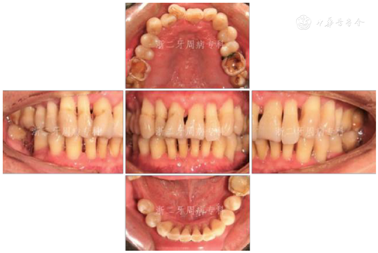

口腔卫生欠佳,软垢指数:2;牙石指数:3;全口牙龈充血红肿;平均牙周探诊深度(PD)7.0 mm,PD≥7 mm的位点占所有检查位点的63.3%(114/180),其中17颊侧远中、17舌侧远中、34舌侧远中、36颊侧近中、46舌侧近中PD深达12 mm;平均附着丧失(CAL)9.3 mm、CAL≥5 mm的位点数为98.3%(177/180);BOP(+)%:100%;37、46松动度Ⅲ度,11~17、21、22、24~27、32、34、41~43、45、47松动Ⅱ~Ⅲ度,余牙松动度Ⅰ度;36、46Ⅲ度根分叉病变。16、26、36、46牙釉质发育不Ⅲ全,11扭转,37缺失舌向倾斜,12、14~16、24、25、41、42咬合时出现异常动度,31、41可见1.5 mm左右牙间隙(图1,图2)。牙髓活力测定:17、34牙髓活力正常,36、37、46"40"无反应。

全口曲面体层X片示:全口牙槽骨广泛性水平吸收,46牙槽骨吸收超过根尖;36根尖周和根分叉区低密度影;13、22、23、33~35、43~45、47牙槽骨吸收达根长1/2~2/3,余牙牙槽骨吸收至近根尖(图3)。